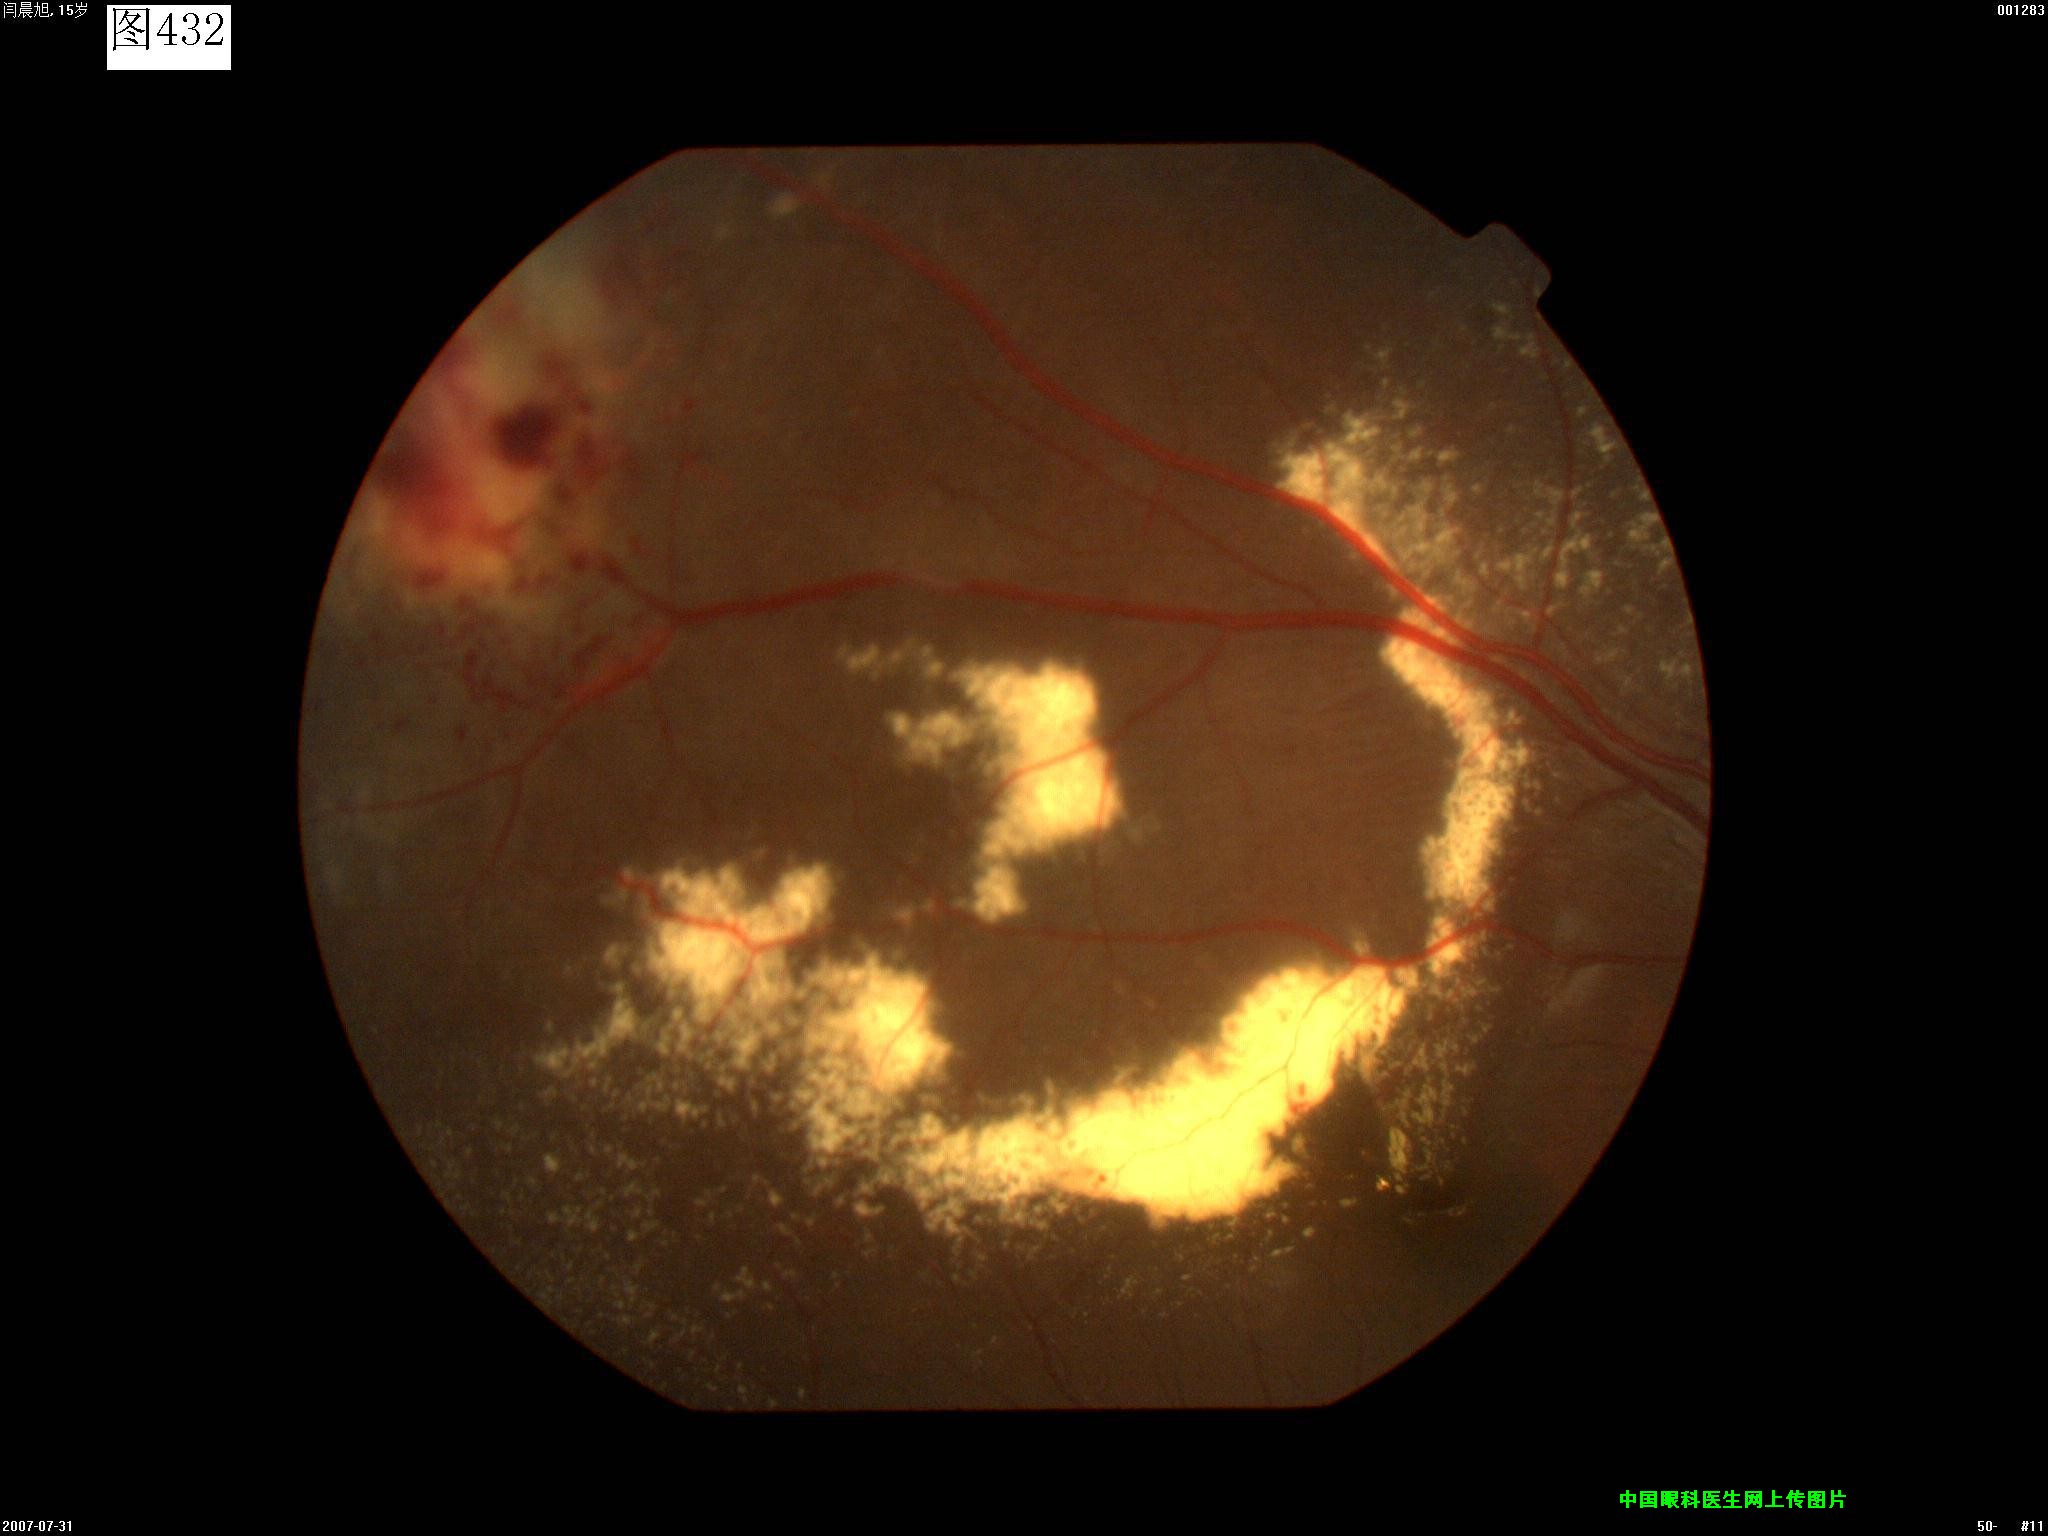

429 430 431 432